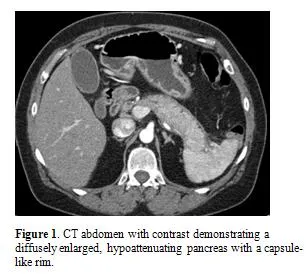

- Imaging: Diffusely enlarged, "sausage-shaped" pancreas with a featureless border and a surrounding capsule-like rim on CT/MRI.

⭐ Type 1 AIP characteristically presents with a diffusely enlarged, featureless, "sausage-shaped" pancreas on imaging and is highly responsive to steroid therapy.